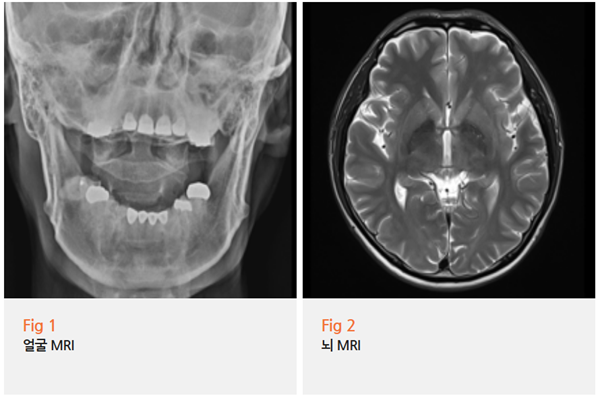

아까 말씀드린 환자분께도 저는 일단 MRI를 권해드렸어요.

"혹시 뇌에 문제가 있는 건 아닐까요?"라고 걱정하시길래,

오히려 그 부분을 확실히 확인하는 게 맞다고 생각했거든요.

3차신경통의 원인 중 하나가 혈관이 신경을 압박하는 경우인데,

이건 MRI로 어느 정도 확인이 가능해요.

그림13.png <해당 환자분의 mri 사진입니다. 정확하게 판별할 수 있는 계기가 되었죠. ^^>

물론 모든 경우에 MRI에서 명확히 보이는 건 아니지만,

최소한 뇌종양이나 다른 구조적 문제는 배제할 수 있죠.

다행히 이 환자분은 MRI상 뇌에 특별한 이상이 없었어요.

기질적인 병변은 없고, 임상 증상과 진찰 소견을 종합했을 때

3차신경통으로 판단할 수 있었어요.